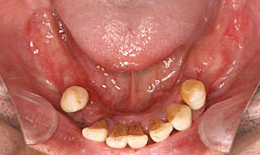

インプラント症例(25)50歳 男性

治療後

上顎

インプラントを6本埋め込んで、ボーンアンカードブリッジを装着した

下顎

インプラントを7本埋め込んで、セラミックスクラウンを被せた